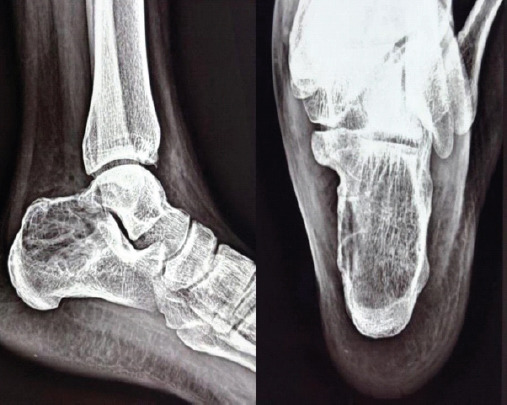

Case report: Benign bone tumors such as GCT are often diagnosed with a symptomatology typical of bone tumors, however, there have been many reported cases wherein they were diagnosed incidentally as part of investigation into a different disease manifestation. These nuances are of more significance in case of GCT as it is a benign aggressive tumor and the prognosis after treatment is highly dependent on earlier diagnosis allowing for increased chances at limb salvage and functional restoration as compared to more radical treatment options.Lateral ankle sprain is a commonly encountered disease entity and, as such, enjoys a very benign progression with conservative management.Our patient was initially diagnosed on outpatient basis as a case of ankle sprain based on the history and clinical features, However, worsening of symptoms on conservative management prompted us toward the presence of a more sinister pathology. Subsequent radiological and histopathological investigations helped in the definitive diagnosis of GCT of calcaneus.